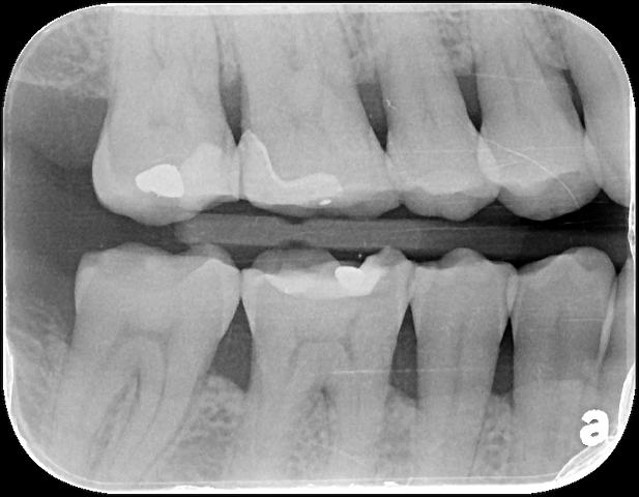

治療後,X光密合度良好